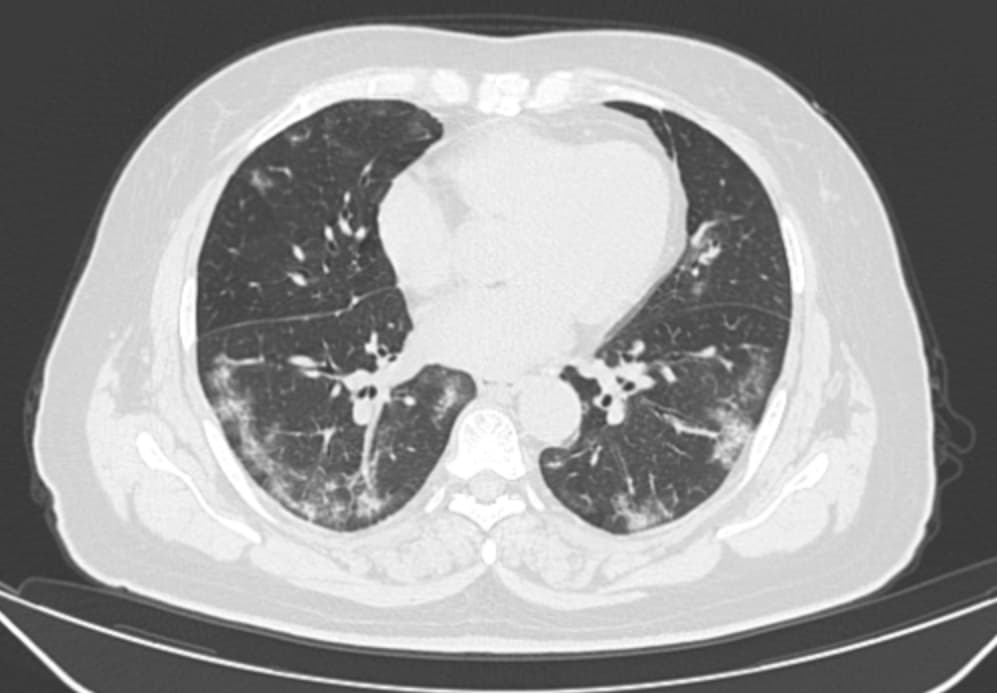

Obligatory features:

- Ground-glass opacities, with or without consolidations, in lung regions close to visceral pleural surfaces, including the fissures (subpleural sparing is allowed) AND

- Multifocal bilateral distribution

Confirmatory patterns:

- Ground-glass regions

- Unsharp demarcation, (half) rounded shape.

- Sharp demarcation, outlining the shape of multiple adjacent secondary.

- Pulmonary lobules.

- Crazy paving.

- Patterns compatible with organizing pneumonia.

- Thickened vessels within parenchymal abnormalities found in all confirmatory patterns.

| Intermediate | 3-5 days | Ground-glass opacities Consolidations Peripheral distribution of disease |